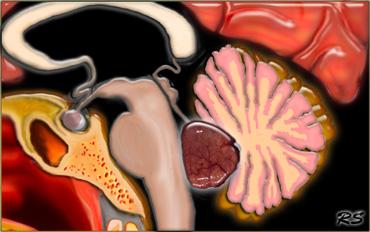

U màng nội tủy (ependymoma) của não thất IV ở trẻ em có xu hướng lan rộng qua lỗ Magendie đến bể lớn (cisterna magna) và qua các lỗ bên Luschka đến góc cầu tiểu não (hình minh họa).